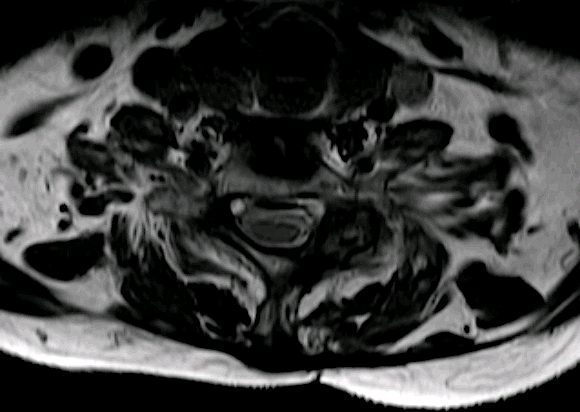

Corte axial C7-Th1

Los quistes facetarios o yuxtafacetarios que causan compromiso de canal son habituales en facetas lumbares pero apenas hay casos descritos en la literatura a nivel cervical y dorsal. Con frecuencia se asocian a otros signos degenerativos de esponsilosis avanzada.